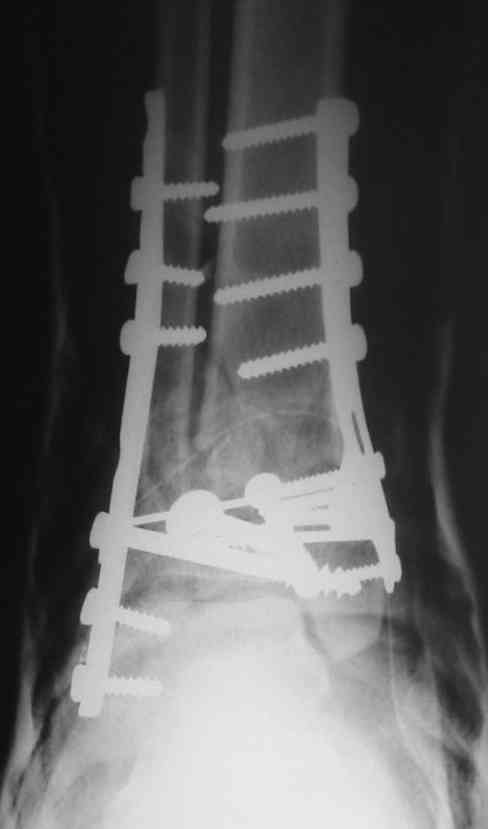

Однозначно сказать сложно.Расстояние между тараном и медиальной лодыжкой меньше чем между тараном и крышей большеберцовой кости.Это может быть за счёт не правильной укладки.Пока не отчаиваетесь.Главное вы поняли принцип.Сделайте несколько проекций прямых и посмотрим.Для всех интересно.С уважением

Мне кажется, что все конечно далеко от идеала. Сложный перелом. Есть ощущение, что малоберцовая кость (ключ!) фиксирована с ротацией и удлинением. Снимки конечно необходимо сделать в правильных проекциях и без гипса...

Применение шурурпов 4.5 мм и более толстых пластин крайне недопустимы. Рекомендуется низкопрофильные, контурированные пластины с шурупами 3.5 мм, а иногда те же 3.5 шурупы но с головкой 2.7 мм.

Примущества Locking plate не только механическая, и еще отсутствует раздражающий фактор на местные ткани, потому что шуруп сидит в пластине заподлицо. Если рана ушита с натяжением и имеется отек, сомневаюсь в помощи от насечек, лучше распустить рану с латеральной стороны, там больше тканей, после спадения отека можно закрыть или в

крайнем случае кожная пластика.